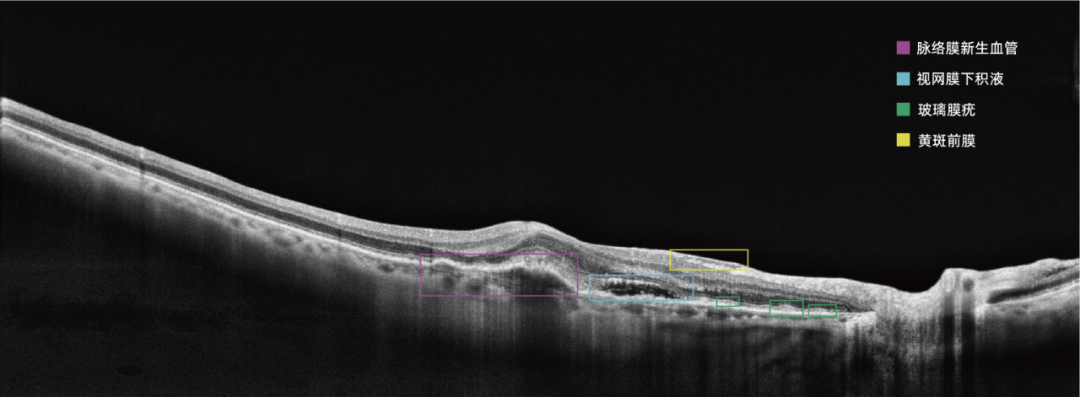

眼底彩照影像为视网膜二维图像,而OCT获取的是视网膜三维结构信息;OCT影像包含的视网膜结构层次信息丰富复杂,AI算法开发的难度较眼底彩照更大。比格威医疗基于OCT影像对年龄相关性黄斑变性(AMD)等十余种眼底疾病的分类、识别、病灶分割算法进行持续研究,取得一系列创新成果,在这一技术领域申请专利70余项,已获授权的发明专利达30余项。